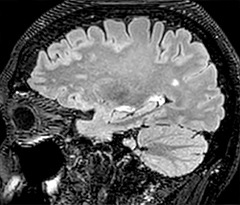

This is an example of acute ischemic stroke with distal occlusion of the right posterior cerebral artery. Note the improved visibility of the ischemic territory on the diffusion weighted image with high b-value. The 3D FLAIR shows a distal PCA occlusion. The fast SWIp depicts the thrombus on the isolated second echo image. The total scan time (including SmartBrain, preparations and a fast 3D T1w TSE Gd) is 8:00 minutes.

In this patient with acute right motor deficit and aphasia, the b2000 diffusion weighted image is normal. The SWIp image demonstrates more prominent veins in the right hemisphere, which could reflect increased deoxyhemoglobin contents. Fast ASL shows low CBF regions in the left frontal lobe. A follow-up ASL after one hour demonstrates high CBF values in the same area. The final diagnosis was migraine with aura.